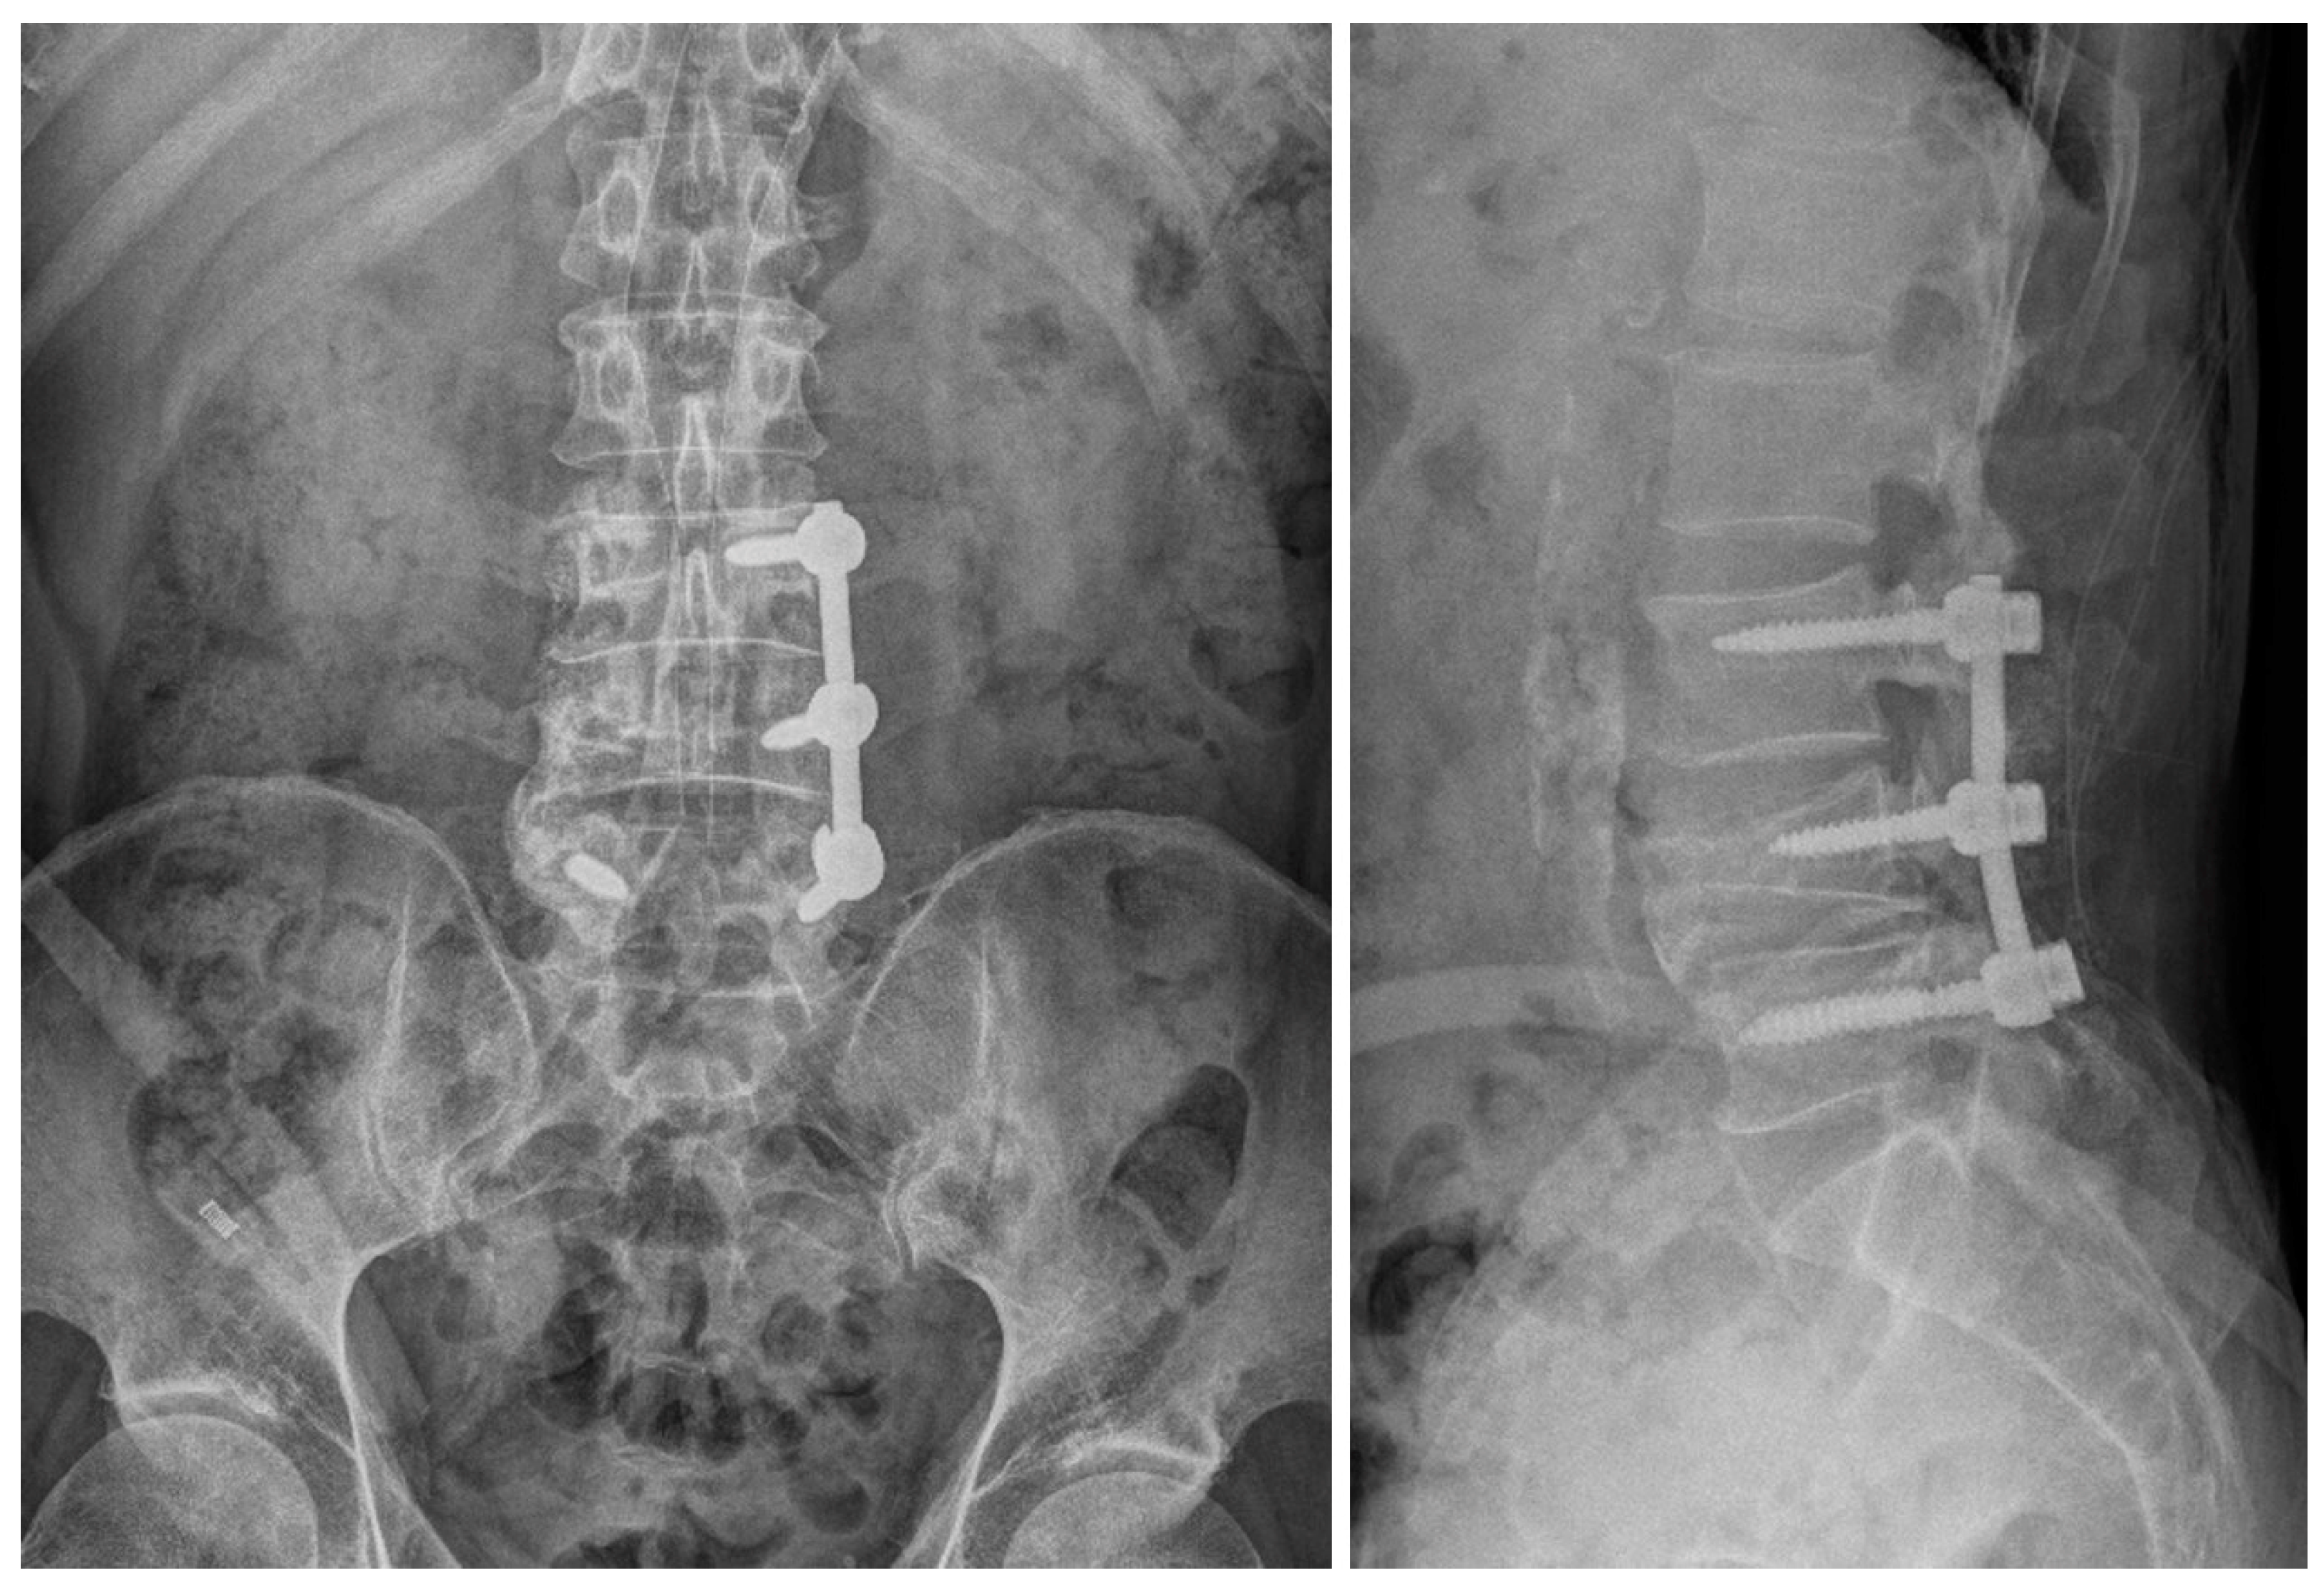

2.1. Case 1